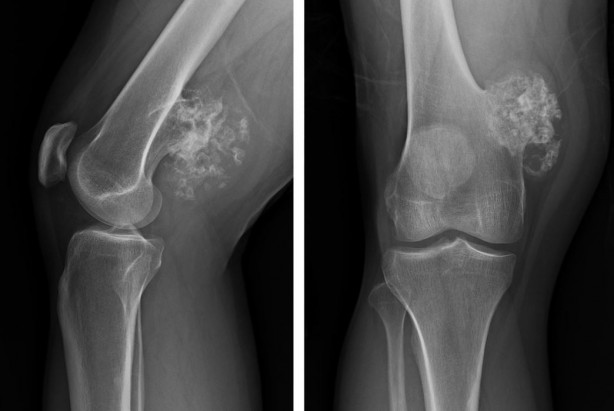

OpenAI'nin GPT-4 LLM'sine dayanan bir yapay zeka modeli olan ChatGPT, beyin tümörlerinin teşhisinde etkileyici beceriler gösteriyor. Osaka Metropolitan Üniversitesi Tıp Fakültesi'nden araştırmacılar, 150 ameliyat öncesi beyin tümörü MR raporunu kullanarak ChatGPT ile radyologların tanı doğruluğunu karşılaştıran bir çalışma yürüttüler.

Sonuçlar ise oldukça şaşırtıcı. ChatGPT yüzde 73'lük bir puan alarak nöroradyologların (yüzde 72) ve genel radyologların (yüzde 68) doğruluk oranını geride bıraktı.

Çalışmada ayrıca ChatGPT'nin tanısal doğruluğunun klinik raporu kimin yazdığına göre değiştiği bulundu.

Nöroradyologların raporlarını yorumlarken, AI modeli yüzde 80'lik bir doğruluk oranına ulaştı.

Ancak genel radyologların raporlarına gelince bu sayı yüzde 60'a kadar düştü.